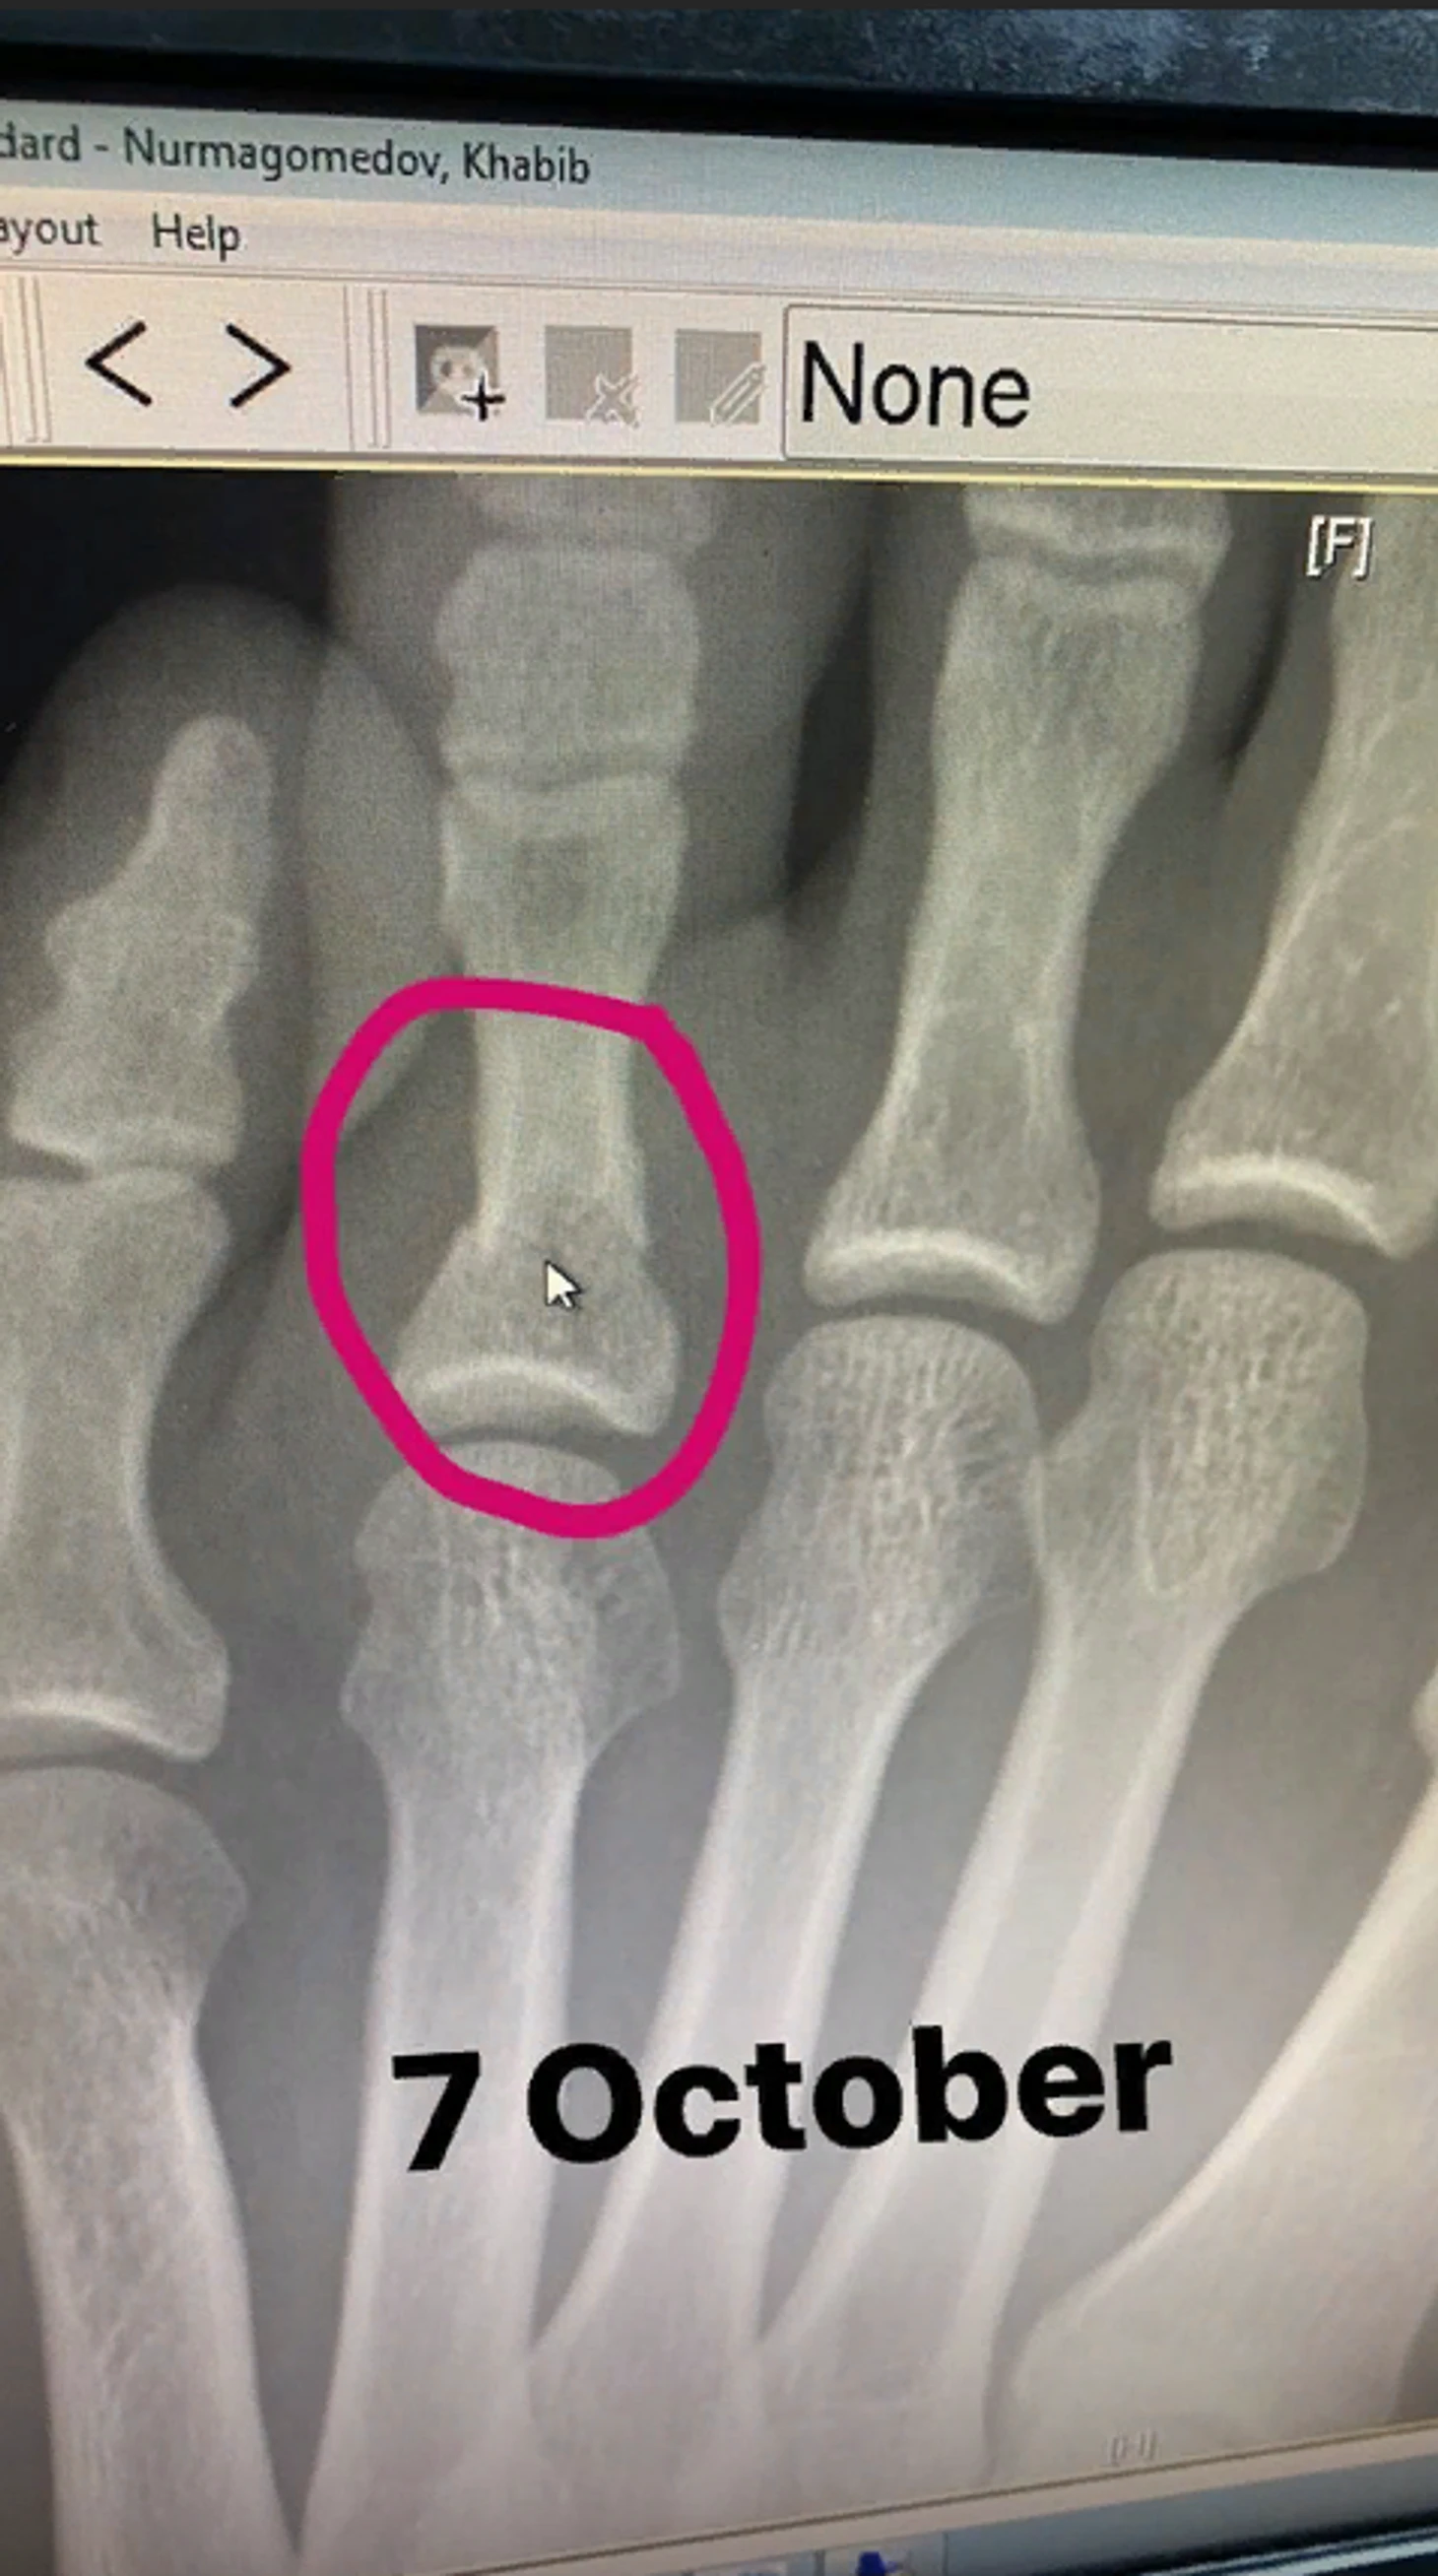

Чемпион UFC в легком весе Хабиб Нурмагомедов получил травму стопы в ходе подготовки к бою с Джастином Гейджи на UFC 254.

Нурмагомедов добавил рентгеновский снимок левой стопы, сделанный 7 октября и фото ноги.